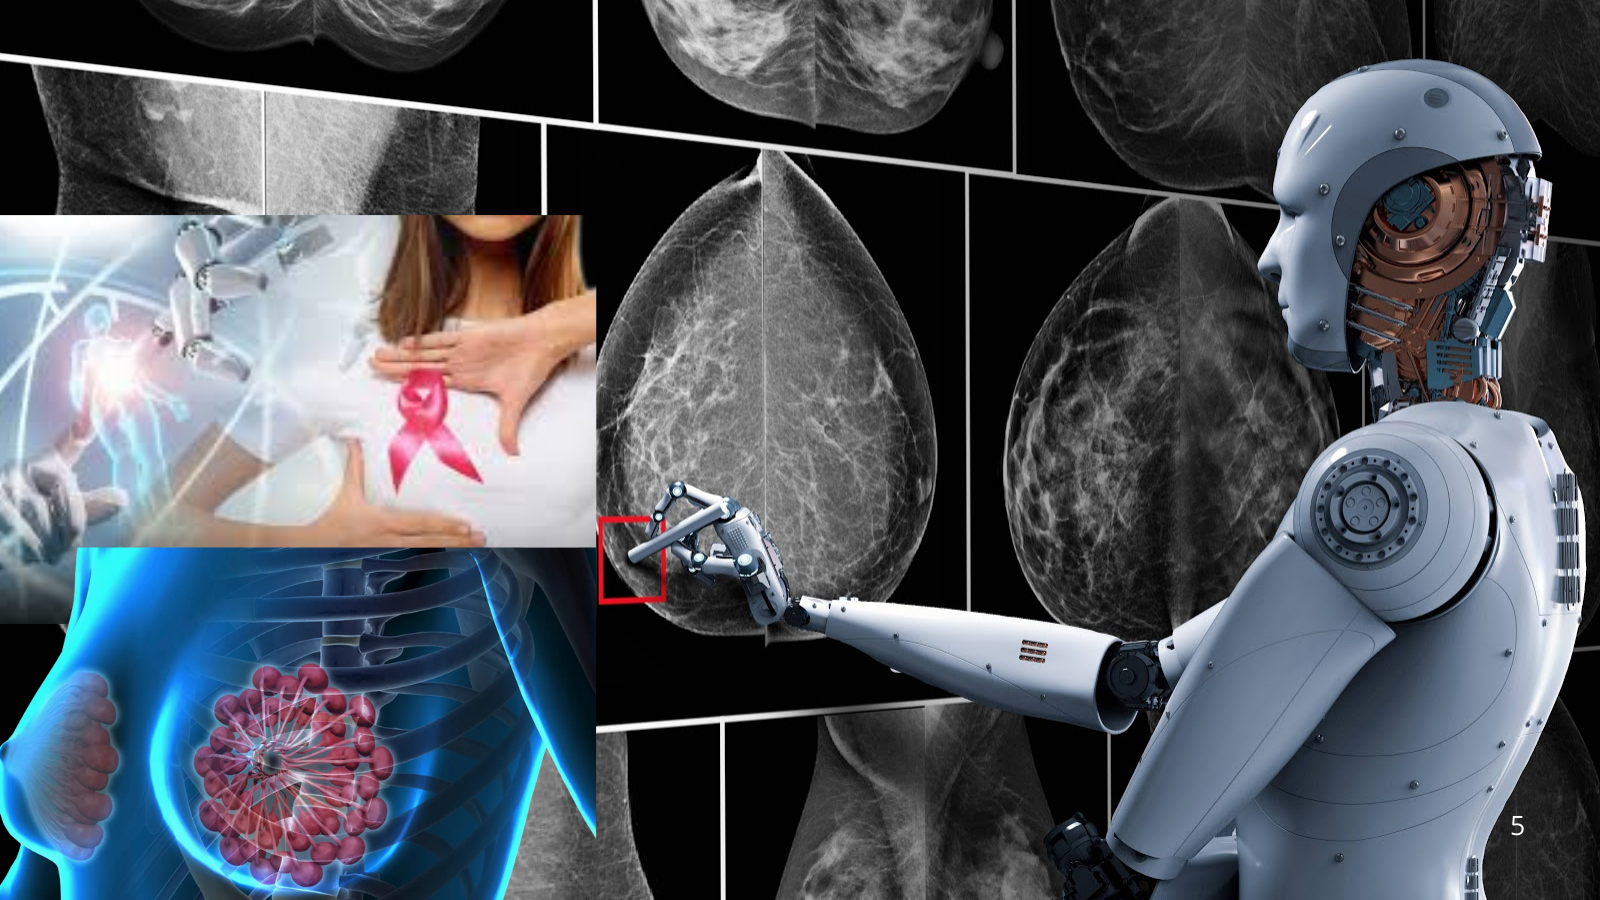

Un estudio realizado en Suecia, con más de 100,000 participantes, encontró que las mamografías asistidas por inteligencia artificial detectaron más casos de cáncer en etapas tempranas y redujeron la aparición de tumores diagnosticados entre evaluaciones. Los resultados fueron publicados el 29 de enero en la revista médica The Lancet.

La investigación incluyó mujeres de entre 40 y 74 años que se realizaron pruebas en cuatro centros médicos entre abril de 2021 y diciembre de 2022. La mitad siguió el proceso tradicional, donde dos radiólogos analizan las imágenes. El resto fue evaluado con un sistema comercial de inteligencia artificial que identificaba zonas sospechosas y definía el nivel de riesgo de cada caso.

El programa asignaba los estudios de bajo riesgo a un solo médico y los de mayor probabilidad a dos especialistas, además de resaltar posibles anomalías en las radiografías. Con este método, se registró una reducción del 12 % en los cánceres de intervalo y una disminución del 16 % en los casos que ya habían invadido tejido sano.

Asimismo, el 81 % de los diagnósticos en el grupo que utilizó inteligencia artificial se detectaron durante los chequeos rutinarios, frente al 74 % en el grupo que siguió el modelo convencional. Investigaciones previas relacionadas con este ensayo también señalan una reducción del 44 % en la carga de trabajo de los radiólogos sin afectar la capacidad de detectar la enfermedad.